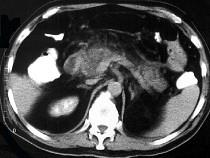

问题 男,32岁,上腹部持续性疼痛,放射至胸背部,高热,恶心呕吐,上腹部压痛反跳痛,CT检查如图,最佳的诊断是 ( )

选项 A.急性单纯性胰腺炎 B.出血坏死性胰腺炎 C.慢性胰腺炎 D.慢性胰腺炎急性发作 E.胰腺癌

答案 B